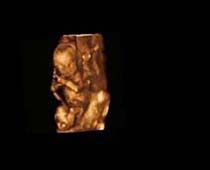

صور لأجنة ثلاثية الأبعاد بجهاز الموجات فوق صوتية | الدكتور نجيب ليوس

صور ثلاثية الأبعاد بجهاز الموجات فوق صوتية